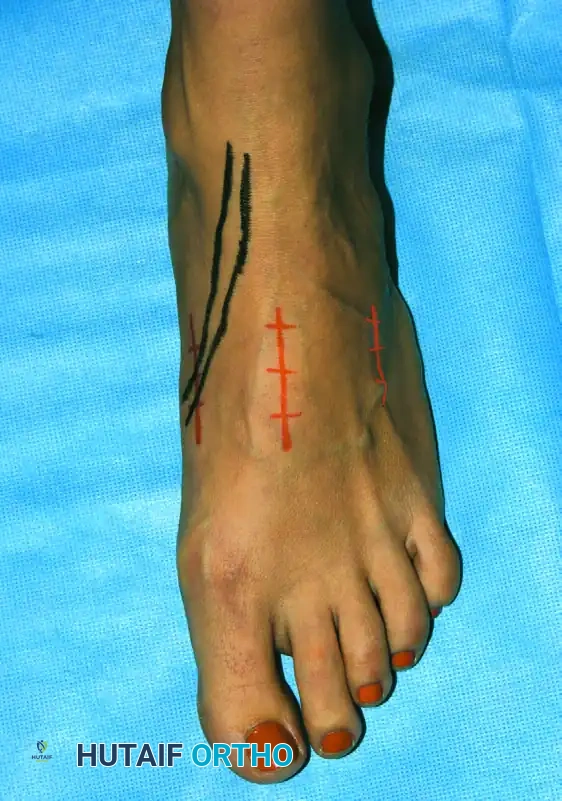

الشقوق الجراحية والوصول للمفاصل

يعتمد عدد وموقع الشقوق الجراحية على المفاصل التي سيتم دمجها.

يتم إجراء شق طولي على ظهر القدم، تحديداً في الجهة الداخلية لمفصل المشط الثاني، للسماح بالوصول إلى المفاصل الرصغية المشطية الأولى والثانية والمفاصل بين العظام الإسفينية. يمكن توسيع هذا الشق إذا كانت المفاصل الزورقية الإسفينية ستُدرج في عملية الدمج.

إذا تم استخدام شريحة معدنية داخلية لتثبيت المفصل، يتم عمل شق داخلي منفصل يمتد من منتصف العظمة المشطية الأولى إلى حديبة العظم الزورقي. أما إذا كانت هناك حاجة للوصول إلى المفاصل الرصغية المشطية الرابعة والخامسة، فقد يتطلب الأمر شقاً إضافياً في الجهة الظهرية الجانبية للقدم.

أثناء فتح الشقوق، يولي الجراح عناية فائقة لحماية الأعصاب الحساسة، مثل الفروع الجلدية للعصب الشظوي السطحي والعصب الشظوي العميق. كما يتم إبعاد الأوتار الهامة، مثل الوتر الباسط لإصبع القدم الكبير، برفق لحمايتها من أي ضرر.